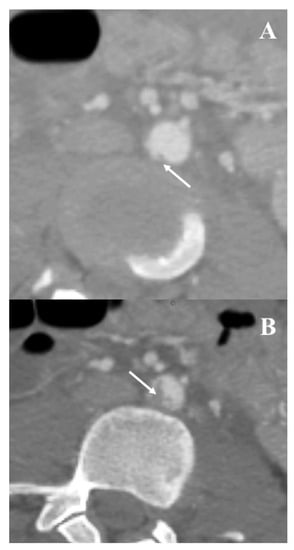

3.3. Institutional Case Report #3—Aortic Injury and Open Surgery for Failed Endovascular Treatment